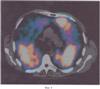

На фиг.1 представлено изображение радиоактивной метки, расположенной на средней трети ключицы в совмещенном трехмерном изображении легких, на фиг.2 представлен аксиальный срез легких на однофотонном компьютерном томографе, где видны участки редуцированного кровотока, на фиг.3 представлен аксиальный срез легких на компьютерном томографе того же уровня, как на ОФЭКТ, где видны участки наибольшего поражения легочной паренхимы, на фиг.4 представлено совмещенное изображение аксиального среза легких.

Двухмерные матрицы срезов ОФЭКТ И МСКТ, полученные в корональной и сагиттальной проекциях, совмещали друг с другом относительно расположения радиоактивной метки на срезе, полученном на гамма-камере, и срезе средней трети ключицы на компьютерном томографе. При совмещении корональных и сагиттальных срезов аксиальные срезы автоматически совмещались. Уровень полученных срезов определялся совмещением радиоактивной метки на ОФЭКТ и средней трети ключицы на МСКТ. На совмещенном изображении корональных, сагиттальных и аксиальных срезов легких было получено изображение зон с нарушенным кровотоком в сопоставлении с изменениями легочной паренхимы.

Совмещение результатов ОФЭКТ и компьютерной томографии (фиг.4) позволило выявить морфологический субстрат изменений перфузии, которые были неспецифичны и изначально могли соответствовать как ТЭЛА, так и хронической обструктивной болезни легких, и были вызваны текущей воспалительной реакцией, проявлявшейся как бронхиолит (выявленный при МСКТ) и сопутствующий ему васкулит. Также дефекты перфузии совпадали с участками максимально выраженной эмфизематозной перестройки легочной ткани. Диагноз ТЭЛА был снят.